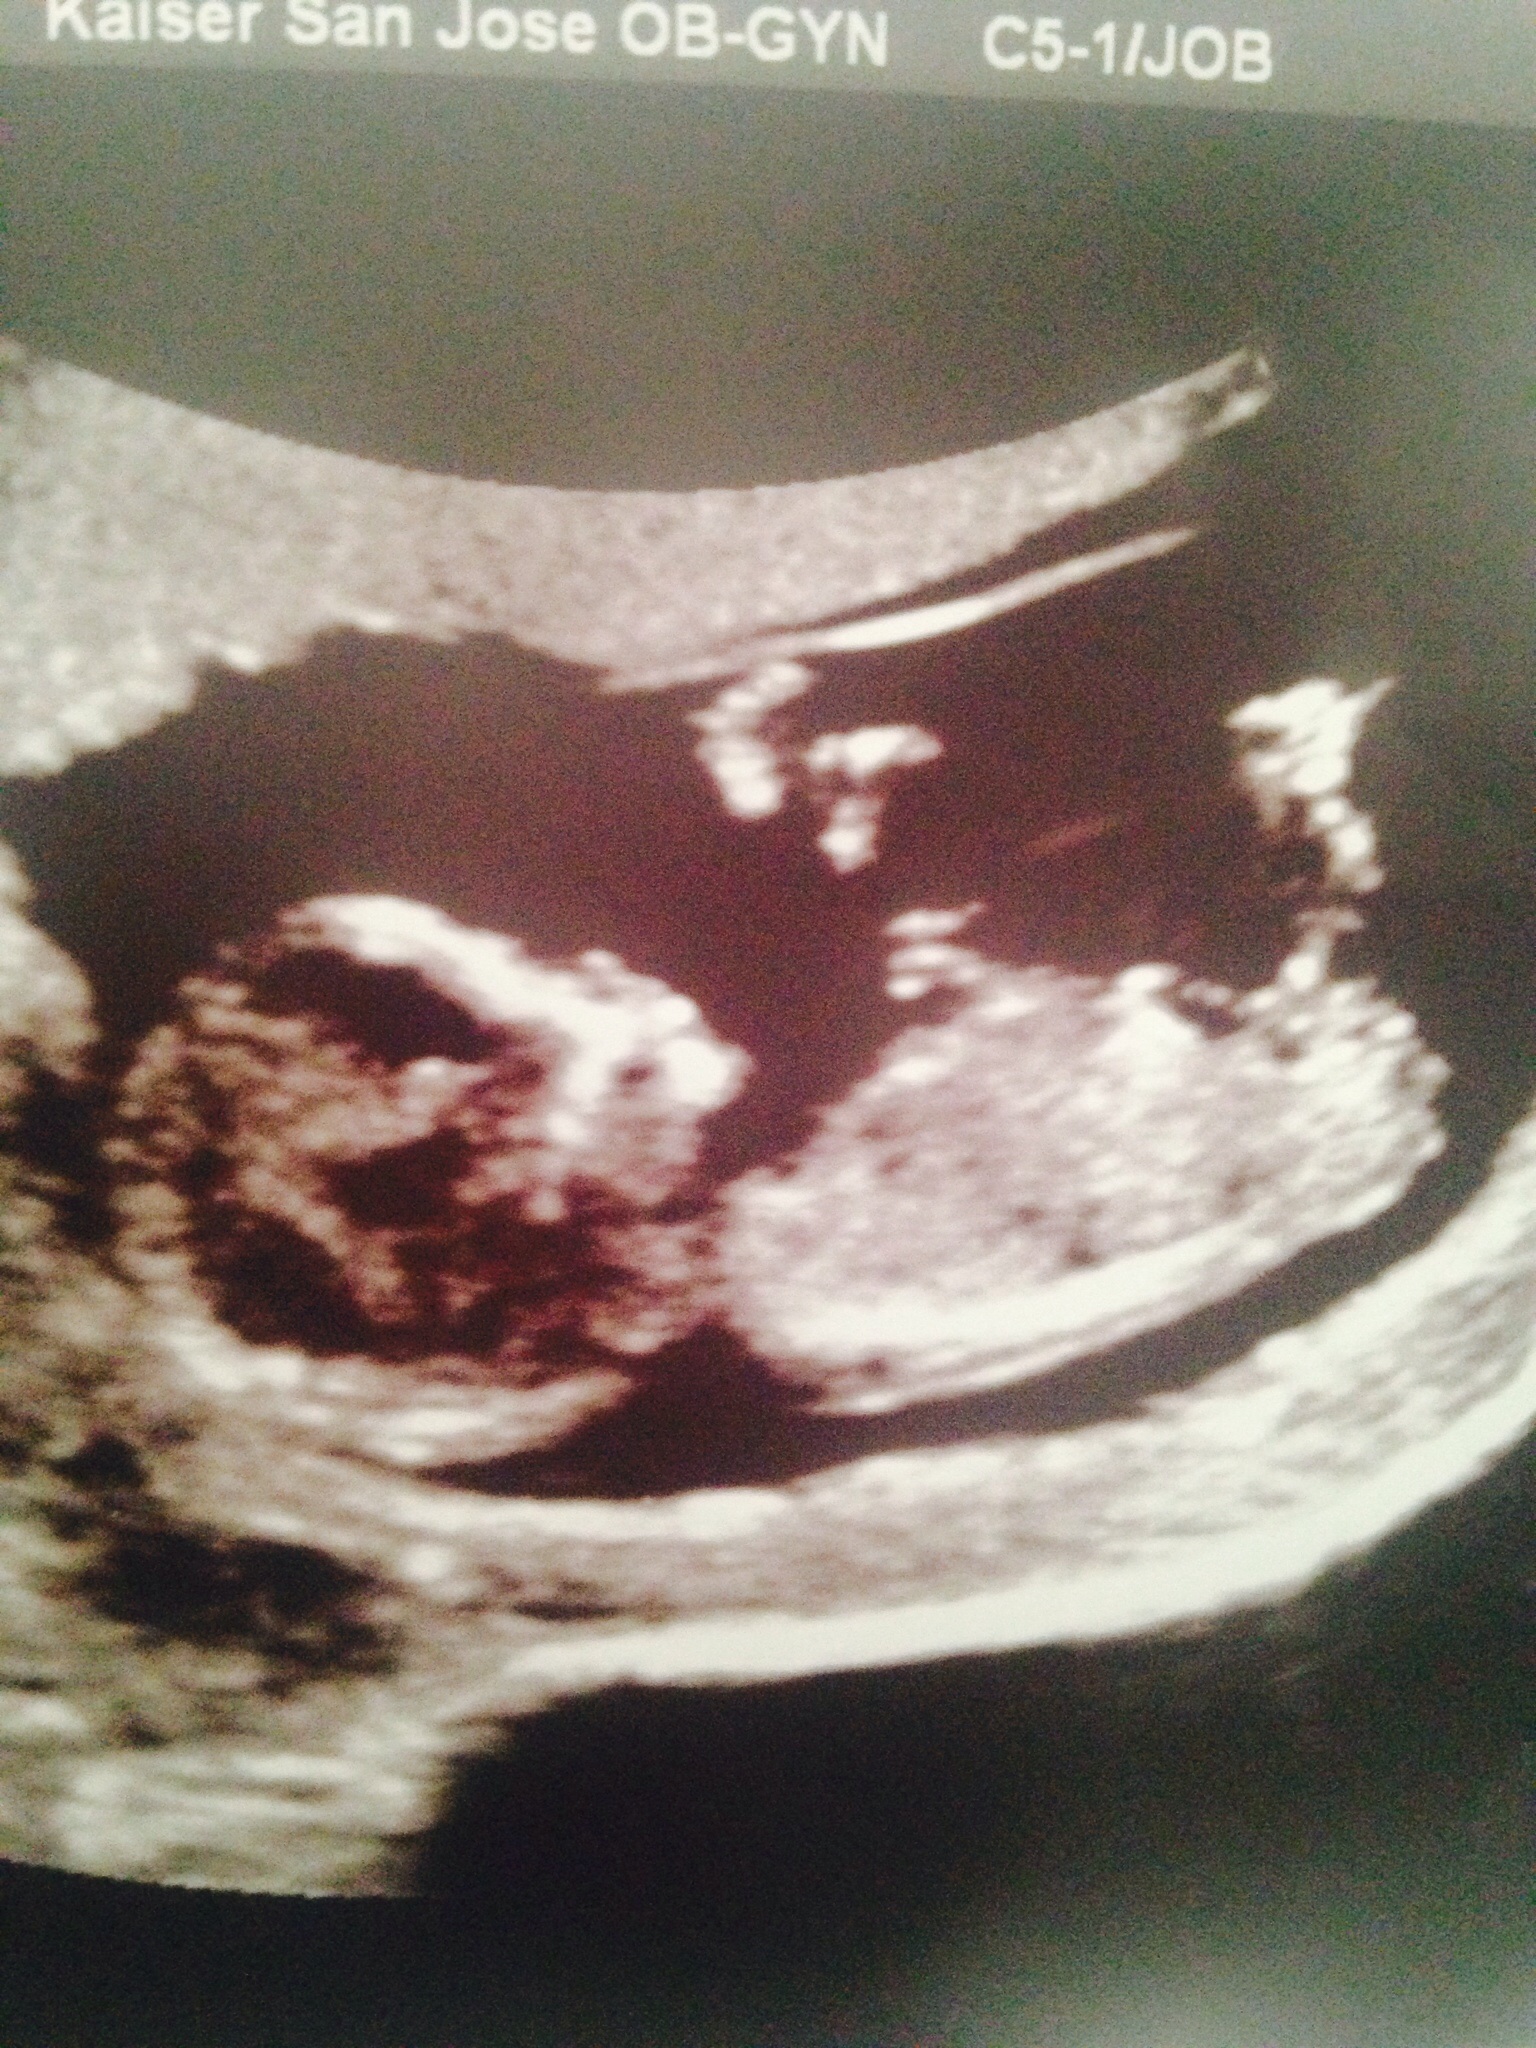

Looks like a boy to me, but I'm no expert

I think boy. That cord is confusing though lying over the nub.

That's what the tech said... That it was just all part of the cord but it kept looking nub like to me during the ultrasound. Of course, I'm no expert either!

Yeah I wouldn't be terribly surprised if it turned into a girl as it's hard to tell where the cord ends and the nub starts.

Here's another one. Not sure if that part sticking up is nub or also part if the cord? Tech insisted cord but I don't know...Attachment 23490